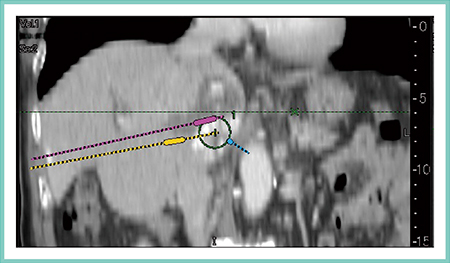

症例3は,Cool-tip針によるオーバーラップ法での活用である。電極針を刺し替えて複数回の焼灼を行うが,腫瘍を含有する形で穿刺ルートの予測を行うと,焼灼範囲のシミュレーションが可能である(図6)。

図6 症例3:Cool-tip針によるオーバーラップ法での活用